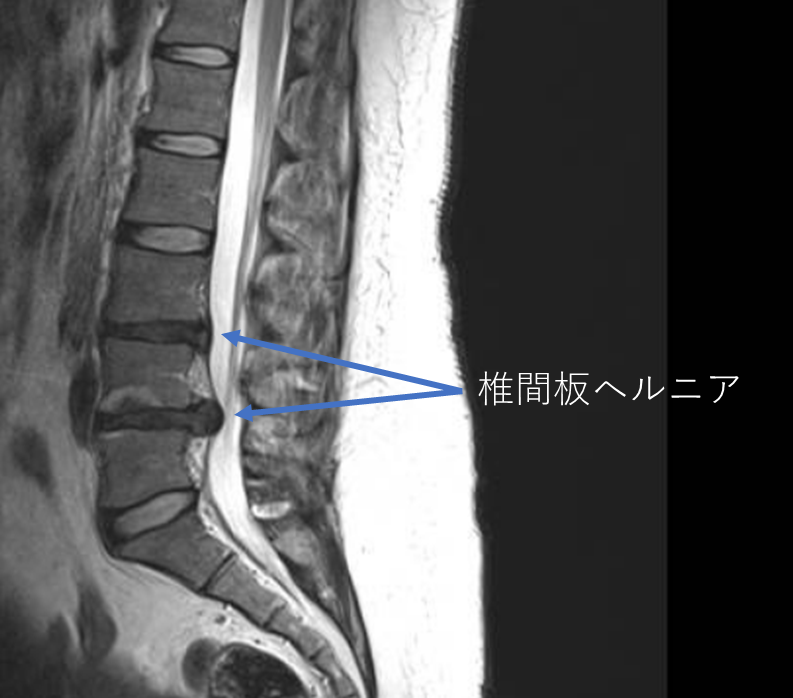

画像及び所見について

- L3/4,4/5-椎間板変性

- L3/4,4/5-椎間板ヘルニア

以上の事が画像上認められます。

・L3/4,4/5-椎間板ヘルニアを認め、主症状の原因の可能性が高い